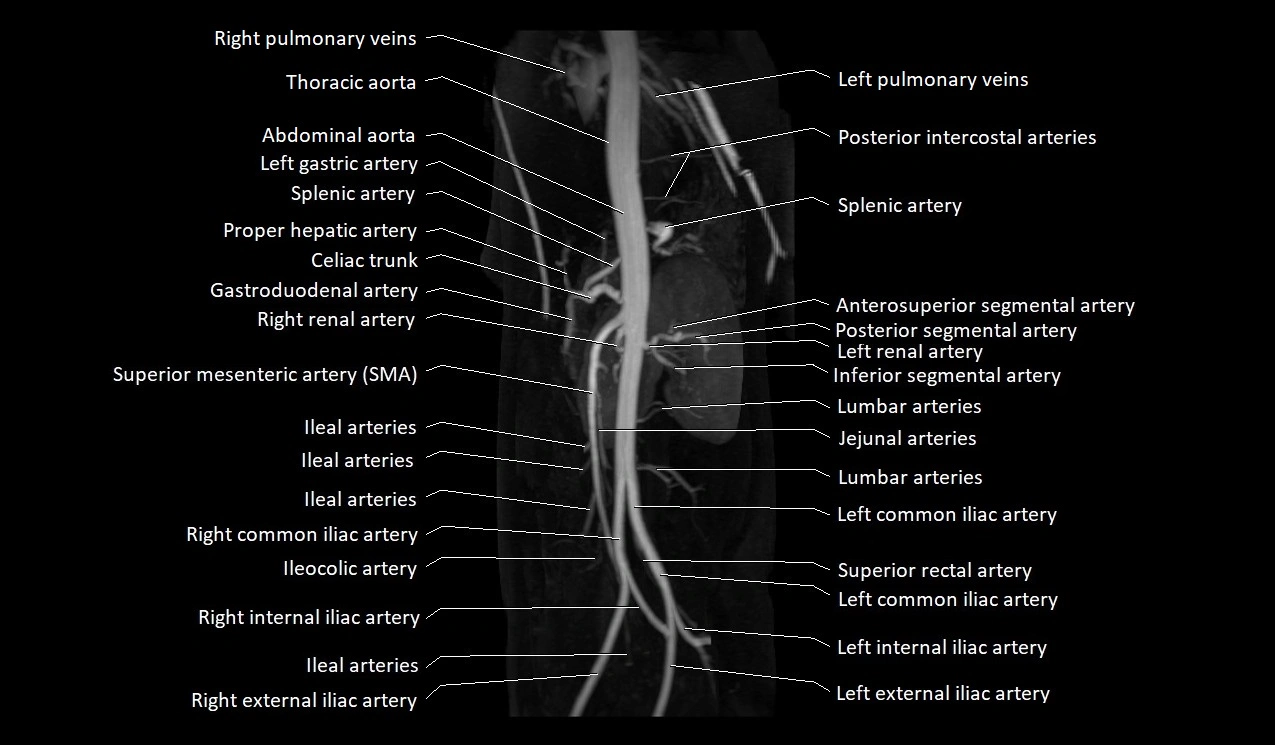

MRA Pelvis with Gadolinium:

-

Clearly delineates the origin, course, and anastomoses of the accessory obturator artery

Identifies connection with inferior epigastric artery, external iliac artery, or obturator artery

Excellent for detecting vascular variants prior to surgery

Useful in mapping pelvic vasculature in trauma, tumor embolization, or preoperative planning